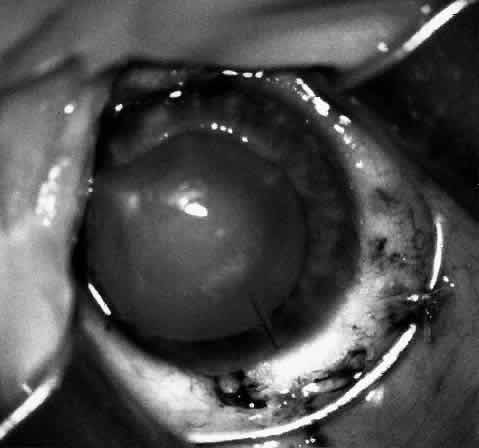

At this point, if intraocular surgery, that is, cataract extraction, pupilloplasty, or membranectomy, is to be done, it is performed through a limbal incision with a vitreous cutting instrument such as the Microvit or Ocutome (Fig. 8). The limbal incision may be closed with 8-0 polyglactin 910 (Vicryl) sutures. After the intraocular procedure is completed and before the epikeratophakia procedure is resumed, it is important to return the eye to normal pressure by injecting balanced salt solution. I prefer to accomplish this with a 30-gauge sharp paracentesis injection through clear cornea.

Fig. 8. After trephination, intraocular surgery may be carried out through a limbal approach if required. Note that the Flieringa ring shown is no longer routinely used.